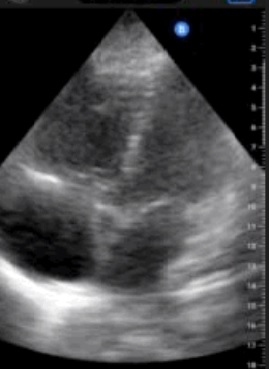

• Ecocardiografía: VD aumentado de tamaño e hipoquinético, AD dilatada. Mínimo Mc. Connell. PEC aplanamiento del septo interventricular en diástole. TAPSE 22 mm.